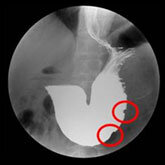

当院は循環器専門病院である一方、予防医学センターでは上部消化管造影検査も行っており、食道や胃に対してバリウムを用いた検査により、病気の早期発見が可能となっております。